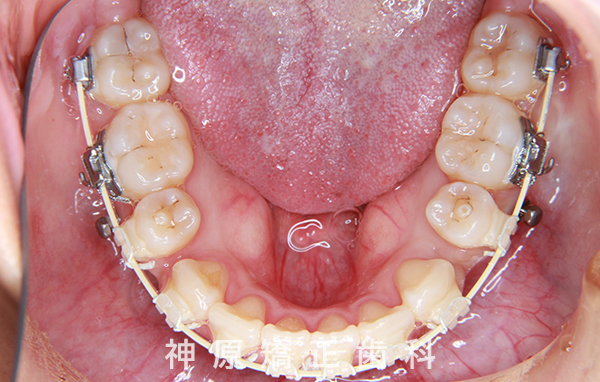

マルチブラケット装着1年後